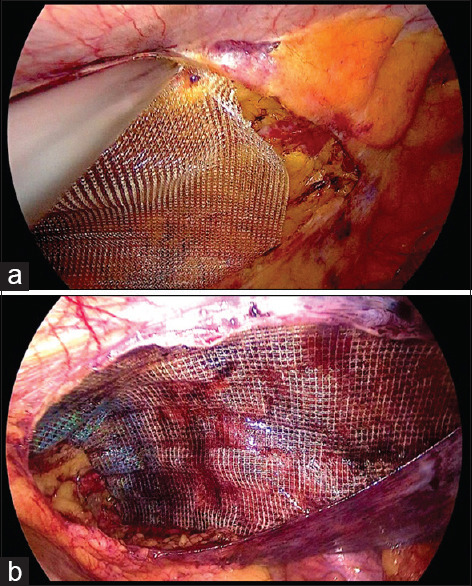

Abstract Image